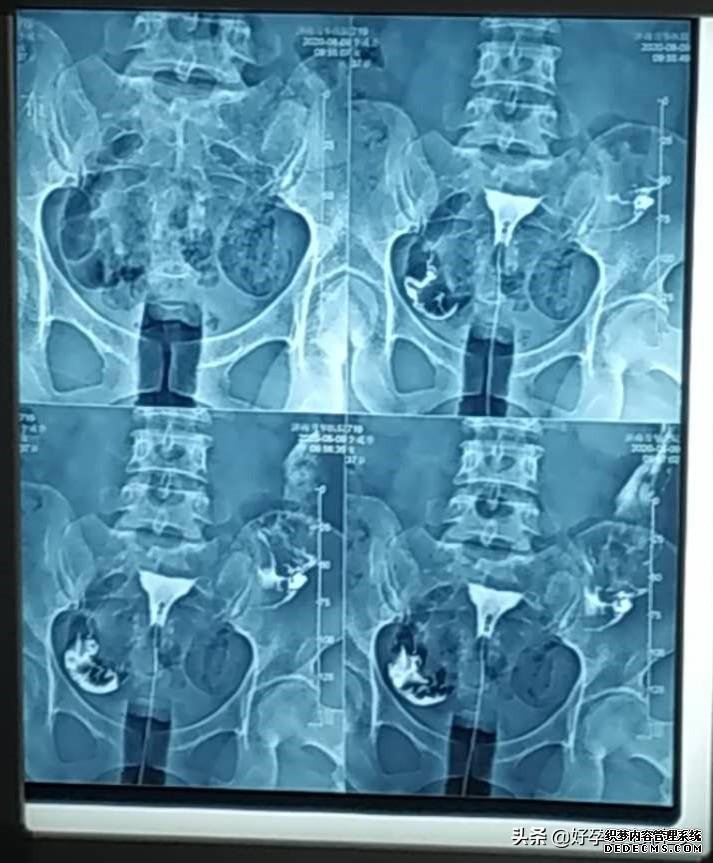

子宮輸卵管造影是通過(guò)導(dǎo)管向子宮和輸卵管注入造影劑,通過(guò)X線來(lái)透視和攝片,然后根據(jù)造影劑在輸卵管和盆腔內(nèi)的造影情況分析輸卵管通暢程度、阻塞的部位和宮腔的情況,是臨床上很多不孕癥女性常做的檢查之一。

正常的子宮輸卵管造影,應(yīng)該是很容易就能把造影劑推進(jìn)去,而且患者不會(huì)出現(xiàn)疼痛等明顯癥狀。現(xiàn)在臨床上的造影劑選用的都是碘水,常用76%的泛影葡胺,滲透壓低,粘稠度低,可以擴(kuò)散到輸卵管的分泌物中,15分鐘就能完成攝片,減少X線照射時(shí)間,注入半小時(shí)以?xún)?nèi)就能被身體吸收,對(duì)女性身體傷害小。

李姐今年33歲,已經(jīng)備孕4年多了,上大學(xué)的時(shí)候做過(guò)一次人流,之后每次月經(jīng)都會(huì)腰痛明顯,但是因?yàn)槟挲g小,以為是痛經(jīng),也沒(méi)有想過(guò)要去醫(yī)院檢查。2016年結(jié)婚開(kāi)始備孕,做常規(guī)的孕前檢查的時(shí)候,B超顯示大量盆腔積液,附件增粗積水,在醫(yī)生的建議下,又做了輸卵管造影,結(jié)果顯示雙側(cè)輸卵管傘端粘連堵塞積水,盆腔炎。